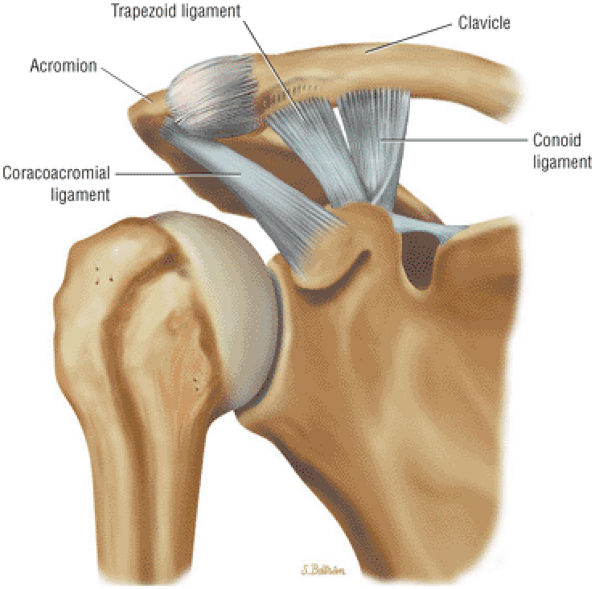

The clavicle connects the axial and appendicular skeletons of the upper extremity.44 It is S-shaped in configuration, with a convex anterior border medially and a concave

P.1195P.1196

anterior border laterally. It is flattened and narrowed laterally and has a thicker cylindrical configuration medially. The clavicle articulates with the sternoclavicular joint medially and with the AC joint laterally (Fig. 8.57). The surfaces of the sternoclavicular joint are covered by fibrocartilage, and a fibrocartilaginous articular disk divides the joint into separate recesses.45 -

The coracoclavicular ligaments are also displayed on anterior coronal oblique images. The anatomy of the AC articulation is best displayed at the level of the supraspinatus tendon. When present, AC joint fluid may represent an asymptomatic manifestation of osteoarthritis.41

inferior surfaces of the acromion. The coracoacromial arch stabilizes the humeral head and prevents superior ascent (Fig. 8.102). The subacromial bursa is located between the acromion, the coracoacromial ligament, and the rotator cuff.44 The bursa runs from the AC joint medially, under the anterior third of the acromion and coracoacromial ligament, to a line that extends approximately 4 cm anterior and lateral to the anterolateral margins of the acromion. Anterior acromial spurs, caused by chronic irritation from the humerus in contact with this ligamentous structure, may form within the acromial portion of the coracoacromial ligament.46 Frequently, anterior acromial spurs are identified adjacent to the acromial attachment of the coracoacromial ligament. The normal low-signal-intensity acromial attachment of the coracoacromial ligament is frequently mistaken for an anterior acromial spur on coronal oblique MR images. The additive thickness of the coracoacromial ligament and the inferior acromial cortex produces this pseudospur (Fig. 8.103). In acromioplasty performed for chronic impingement, the coracoacromial ligament and the anterior inferior margin of the acromion are resected.